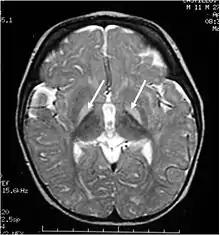

Brain MRI. Hyperintense basal ganglia lesions on T2-weighted images.

These impairments are associated with lesions in the basal ganglia, auditory nuclei of the brain stem, and oculomotor nuclei of the brain stem. Cortex and white matter are subtly involved. Cerebellum may be involved. Severe cortical involvement is uncommon.